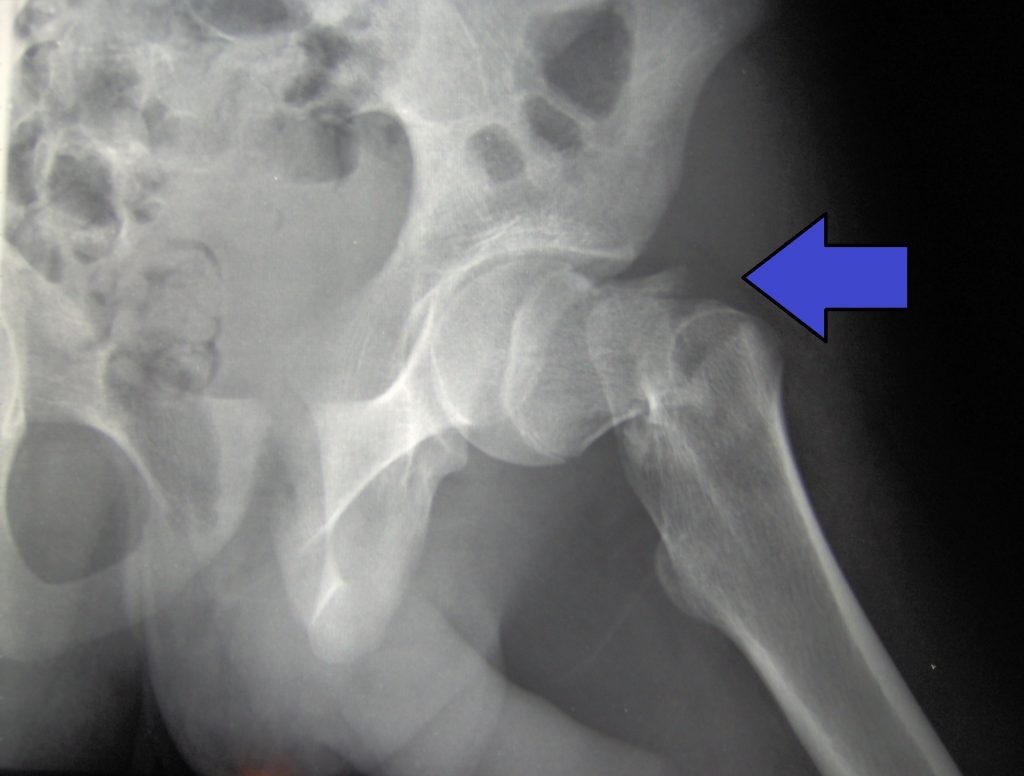

Es en este punto donde se puso en marcha el TERCER GRAN AVANCE: la prevención. Se comenzó a estudiar la resistencia de los huesos y a tratar la osteoporosis. La osteoporosis es la fragilidad ósea propia del envejecimiento, muchas veces ligada a la menopausia. Las densitometrías determinan la cantidad de hueso y, en el caso de osteoporosis, se inicia tratamiento con distintas sustancias. Ahora ya es muy común el tratamiento con bifosfonatos, teriparatida, vitamina D u otros. Esta prevención ha ahorrado muchas fracturas de fémur a la gente mayor hasta la fecha, pero tiene el inconveniente de que tarda meses o años en recuperar la consistencia adecuada del hueso y durante este tiempo los huesos frágiles pueden sufrir la maldita fractura.

Actualmente tenemos la posibilidad de mejorar la resistencia del hueso y prevenir las fracturas de las personas mayores. Lo hacemos con una simple inyección dentro del hueso de una sustancia cálcica especial que le fortalece y estimula su regeneración. Este efecto es inmediato, a diferencia de la medicación, que tarda meses o años en conseguirlo. También sabemos que un porcentaje elevado de pacientes que han sufrido una fractura por osteoporosis sufrirán una segunda o una tercera con más facilidad que la población que tiene osteoporosis pero que no ha tenido fracturas. Es por eso que este grupo de personas que ya han tenido fractura por osteoporosis (fractura vertebral, de muñeca, de fémur, etc.) son las personas que se han de vigilar más. También hay que ayudarlas con una prevención immediata de sus fémures.